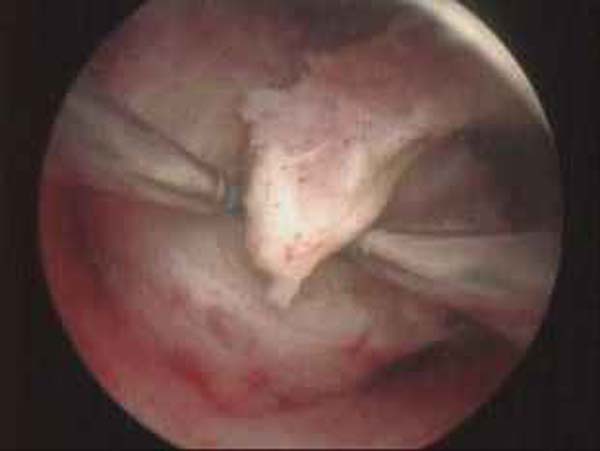

- Hystéroscopie - Hystéroscopie pour l'infertilité

- Résection hystéroscopique d'un septum utérin pour fausses couches à répétition

- Photos de l’hystéroscopie